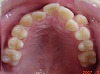

矯正前

s-070216 upper teeth cut.jpg

s-070216 lower teeth cut.jpg